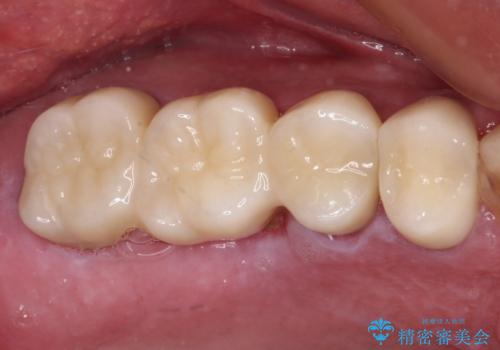

左側は大臼歯2本と小臼歯1本が欠損しているため、インプラント2本を治療したブリッジ、右側は中間欠損であり、前後の歯も加療が必要であったためブリッジによる補綴治療を行うこととしました。

左右同時に強大な力を受けながらの治療であったため、仮歯の脱落や破損などがひんぱつしました。

治療後の現在は、より長い期間安定した状態を維持していただくため、就寝時マウスピースを装着するようお願いしております。